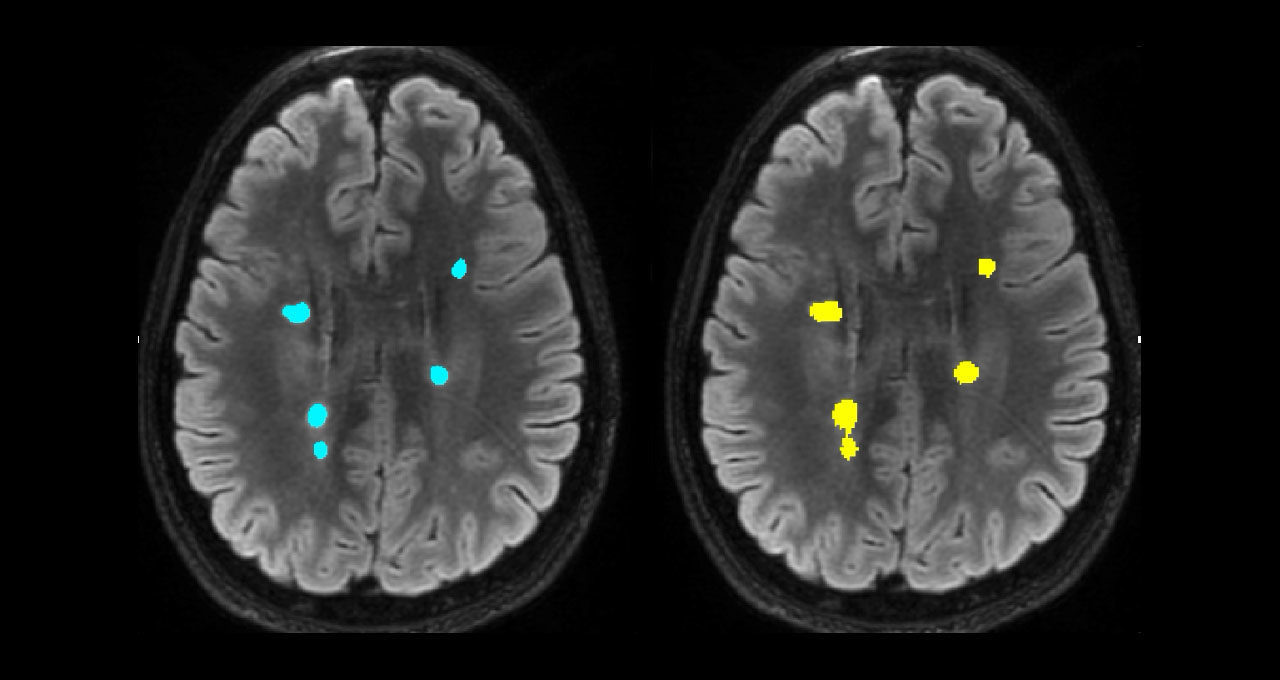

另一個工具可處理多發(fā)性硬化癥病例的大腦病灶分析。在研究和臨床試驗中,影像分析師通常會分割大腦病灶,并通過手動檢查掃描來確定其大小,這一過程要耗費長達 15 分鐘。

AI 可將確定病灶大小所需的時間縮短為 3 秒。這就使得這些指標也可以用于臨床實踐,以往由于時間限制,放射科醫(yī)生通常只通過眼睛簡單觀察來估計病灶大小。

主圖顯示了多發(fā)性硬化癥病灶分割的并排對比。左圖顯示的是手動病灶分割,右圖顯示的是全自動病灶分割。圖片由悉尼神經(jīng)影像分析中心提供。